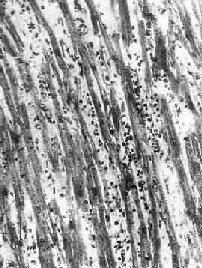

本病病变依患者年龄不同而有所不同。妊娠最初3个月的胎儿感染风疹病毒时,可引起心内膜下心肌的无反应性心肌细胞坏死。在妊娠后期,胎儿感染柯萨奇病毒时则可引起全心炎,大多伴有心骨膜纤维弹性组织增生。初生儿的病毒性心肌炎可见到心肌细胞坏死及粒细胞浸润。其后,代之以巨噬细胞、淋巴细胞、浆细胞浸润及肉芽组织形成(图8-41)。在成人,多累及心房后壁、室间隔及心尖区,有时可累及传导系统。镜下,主要病变为坏死性心肌炎。晚期,可见到明显的心肌间质纤维化,伴有代偿性心肌肥大及心腔扩张(充血性心肌病)。

图8-41 病毒性心肌炎

心肌间质内有弥漫性淋巴细胞及组织细胞浸润